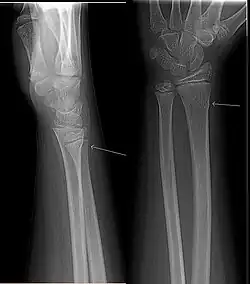

Uma fratura em galho verde é uma fratura em um osso jovem e suave que dobra e parcialmente quebra. O nome é uma analogia com um galho verde de madeira que similarmente quebra quando a parte de fora é dobrada.